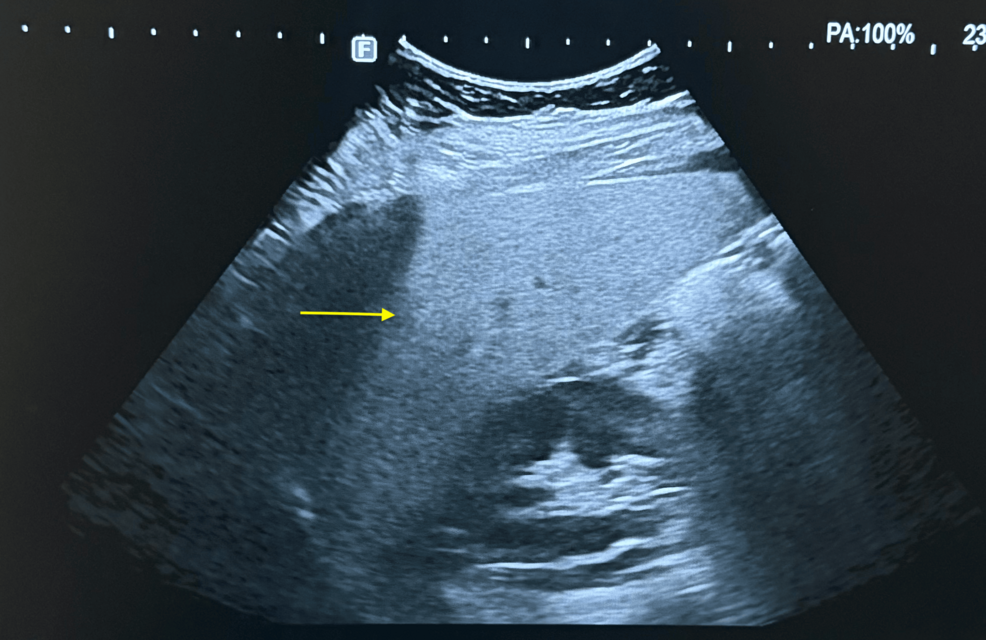

- Ultrasound – Luminous hepatic echotexture with focal fatty sparing is typical for MASH; AIH usually shows normal echogenicity.

- Transient Elastography (FibroScan) –

- CAP score > 280 dB/m → steatosis (MASH).

- LSM > 12 kPa can indicate advanced fibrosis but does not differentiate etiology.

- MRI‑PDFF – Quantifies hepatic fat fraction; > 10 % strongly suggests metabolic steatohepatitis.

- MRCP – Excludes biliary tract disease when AMA‑M2 raises suspicion for PBC.

practical tip: Combining CAP (steatosis) with LSM (fibrosis) improves the pre‑biopsy probability that the underlying process is metabolic rather than autoimmune.